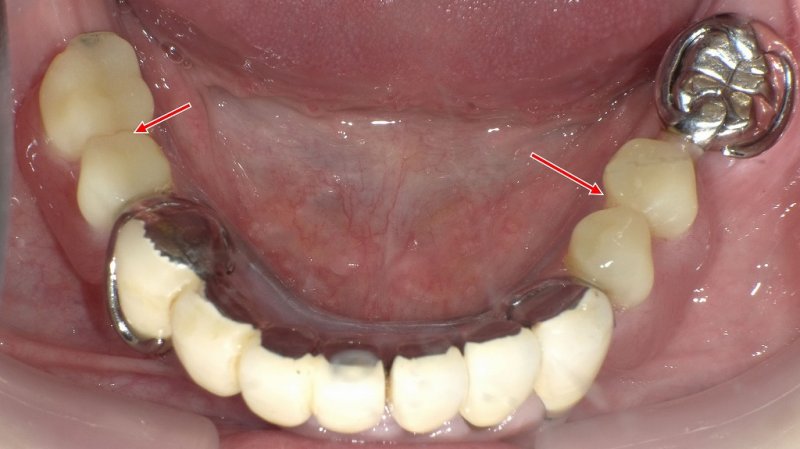

入れ歯(義歯)は、歯を失った部位の咀嚼機能や発音、審美性を回復するための補綴治療の一つです。部分的な欠損を補う「部分入れ歯」と、すべての歯を失った場合に使用する「総入れ歯」があります。

部分入れ歯は40〜50代に多く、残存歯を活かした設計が可能です。